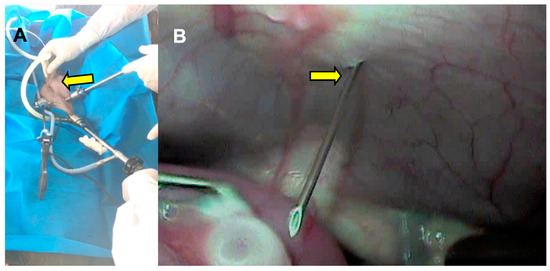

The transabdominal 20 G needle (Figure 7) associated with a pressure of 50 mmHg had a recovery rate of 60.3% (Figure 8).

Figure 7.

(A) Transabdominal use of the aspiration needle (arrow), caudal to the transverse plane formed by the right and left ports. (B) Video-assisted entry of the aspiration needle (arrow) into the abdominal cavity.

The suction set consisting of a 20 G needle and an aspiration pressure of 50 mmHg is similar to that used in buffalo species, in both adult and prepubertal individuals [11,12,28]. The recovery rate was below the 84.3% ± 29.3% obtained in buffalo calves [12] but within the results obtained in small ruminants [17,25]. However, the quality of oocytes recovered was lower than that observed in Mediterranean buffalo heifers with 16.2 ± 9 viable oocytes [11].